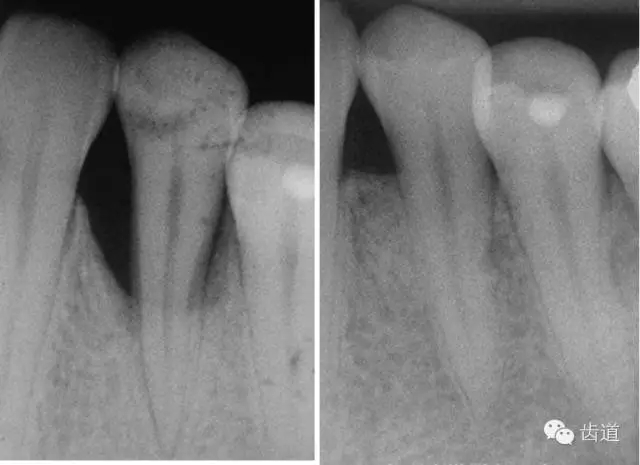

1、垂直型骨缺損:垂直性吸收形成的骨下袋,三壁袋和二壁袋的效果好,一壁袋的效果最差;

2、根分叉病變:II度或III 度根分叉病損, II度效果最好;

如術(shù)區(qū)患牙無咬合創(chuàng)傷;為垂直性骨吸收且在III度以內(nèi);殘留骨壁數(shù)目多(三壁骨下袋);骨缺損窄而深(角度<250°,深度>3mm);牙齦組織較寬且厚度 >1mm(抗張強度大及血供充分)時;則臨床附著水平和骨量增加顯著。另外,根據(jù)病損牙位的特征(前牙、后牙、鄰間隙、根分叉等)選擇不同形狀、大小的屏障膜也很重要。

完成基礎(chǔ)治療(齦上潔治、齦下刮治)且牙周炎癥已控制后2~6周,方可考慮進(jìn)行GTR。若炎癥未控制就進(jìn)行手術(shù),可導(dǎo)致手術(shù)時出血多、視野不清晰和術(shù)后牙齦退縮及膜暴露等問題出現(xiàn)。